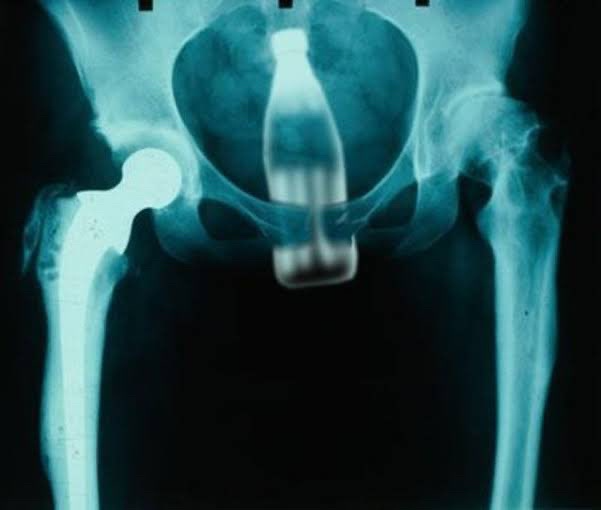

「沒注意放在椅子上的寶特瓶,坐下去插進肛門的病例」

https://i.imgur.com/dwb3wSb.jpeg